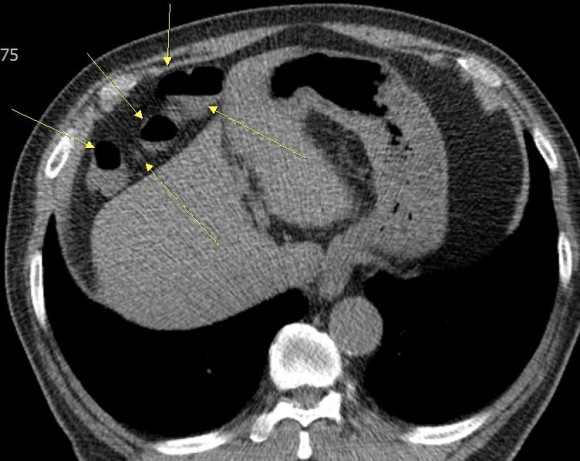

최근 이분의 여러 사진을 검토하는 과정에서 위 사진처럼 횡격막과 간 사이에 대장이 끼어 있는 것이 관찰되었으며, 이 마직막 사진에서는 그 부분의 대장에는 장의 약간의 마비를 시사하는 수면을 볼 수 있다.

이 분의 증상이 이른바 Chilaiditi 증후군이 아닐까 의심된다.이 분처럼 대장이 횡격막과 간 사이에 끼어 있는 현상을 Chilaiditisign이라고 한다. 이것이 확실한 증상을 가져온다는 것이 확인되면 Chilaiditi 증후군으로 진단한다. 그러나 이 병은 진단이 매우 어렵고 증상도 다양하다.

이 병은 19010년 그리스 방사선 의사인 Dimitrios Chilaiditi가 처음 기술했다 뚜렷한 증상은 오른쪽 윗배가 아픈데 다른 병으로는 설명할 수 없으며 이런 현상이 보이자 이 병을 의심한다

그러나 이처럼 대장이 치아에 끼어 보이는 경우는 비교적 적지 않고 만약 간경화가 심하면 간이 위축돼 이럴 수 있다며 이 현상을 보면 간질환을 의심해 볼 정도였다.